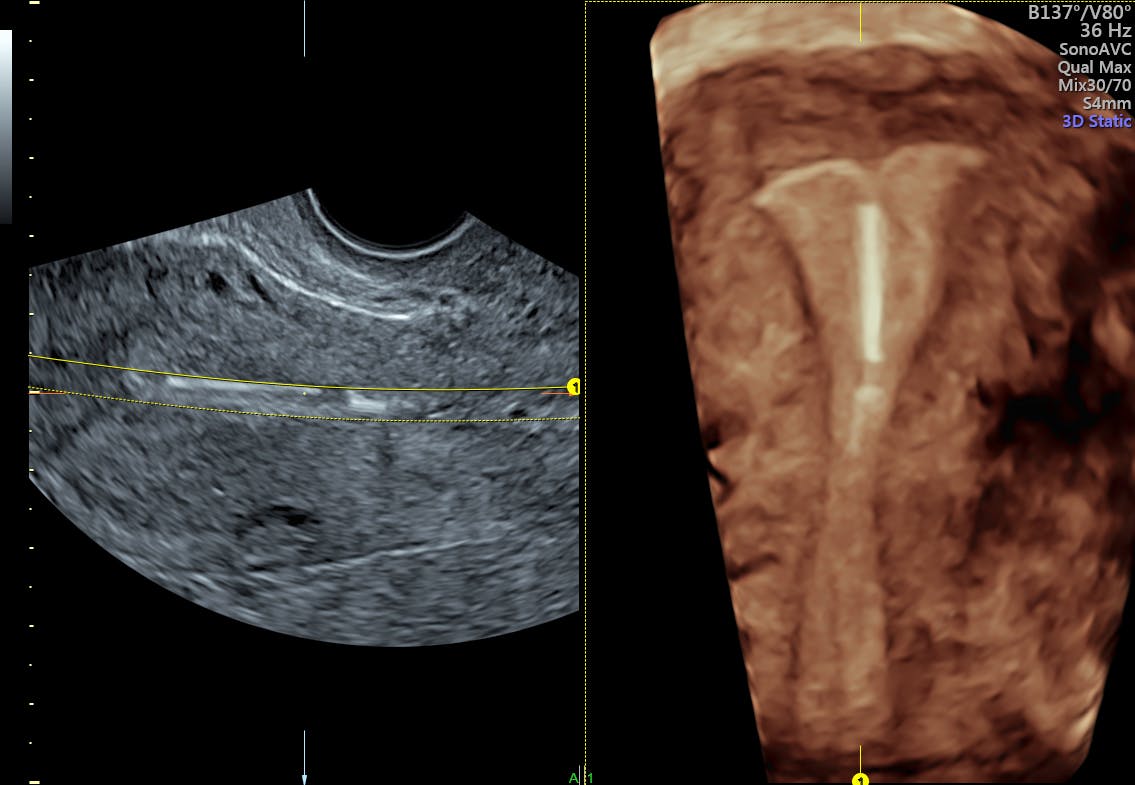

Don't use a menstrual cup with an iud. The intrauterine device (iud) is an effective contraceptive for many women. The iud can sometimes slip out of your uterus — it can come all the way out or just a little bit. An iud is an intrauterine device made of plastic and/or copper that is inserted into the womb (uterus) by way of the vaginal canal. An iud may lower your risk of pregnancy, but your risk of stds is the same.

Britney's iud story is the legacy of that case. and even more details: Iuds also prevent a fertilized egg from attaching to the uterus and developing into a fetus. The copper iud is designed to stay in place for up to 10 years and the hormonal iud (mirena) for 5 years. An intrauterine device (iud) is a small contraceptive device that is put into the uterus (womb) to prevent pregnancy. Don't use a menstrual cup with an iud. An iud is an effective way of preventing pregnancy in the long term. The iud can sometimes slip out of your uterus — it can come all the way out or just a little bit. If this happens, you can get pregnant.